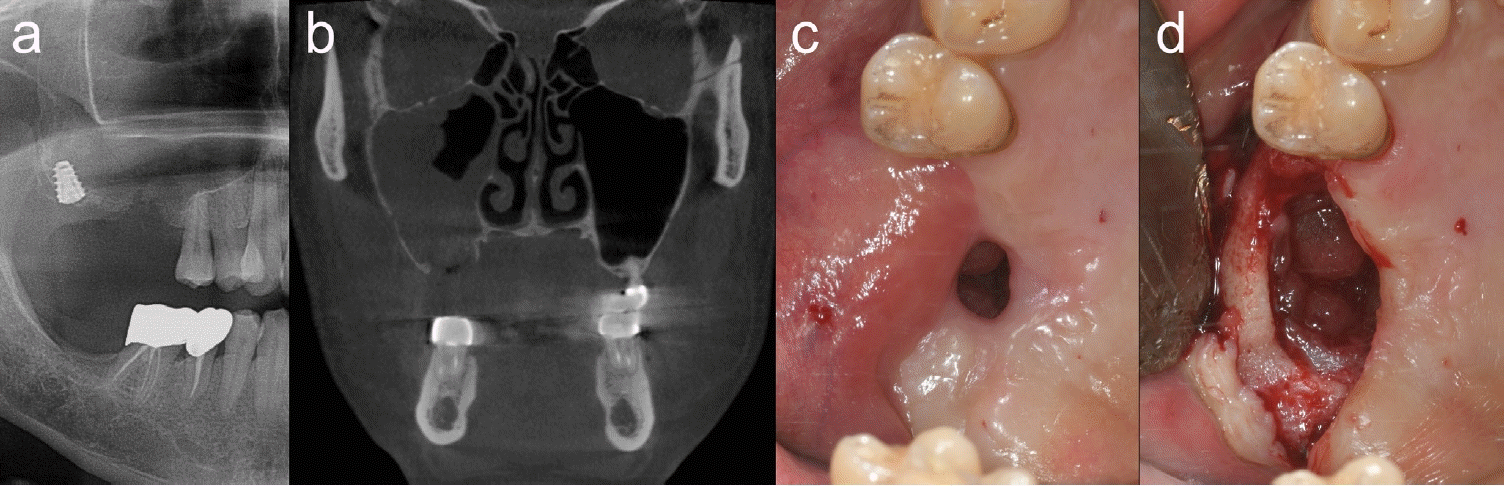

Figure 1.

Clinical and radiological findings at the patient's first visit and first operation. a. Panoramic radiograph at the first visit showing a mal-positioned implant fixture and alveolar bone perforation. b. Computed tomography at the first visit demonstrating a large alveolar bone perforation and inflamed sinus mucosa. c. Intraoral photograph at the first visit revealing an oroantral fistula. d. Inflamed sinus mucosa observed through the extended alveolar bone perforation after raising the gingival flap to manage the sinusitis and close the fistula.